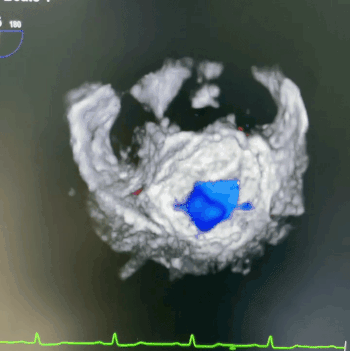

术中超声

此次手术经心尖入路,在纯超声引导下完成,术者以其精细的手术操作成功完成心肌穿刺并将导丝送至左心房,输送系统在导丝引导下进入左心房,在二维及三维超声引导下完成同轴定位、D型定位后,完全释放瓣膜,逐步撤出输送系统,再使用心尖固定系统根据血压调整瓣膜张力,进行心尖固定。